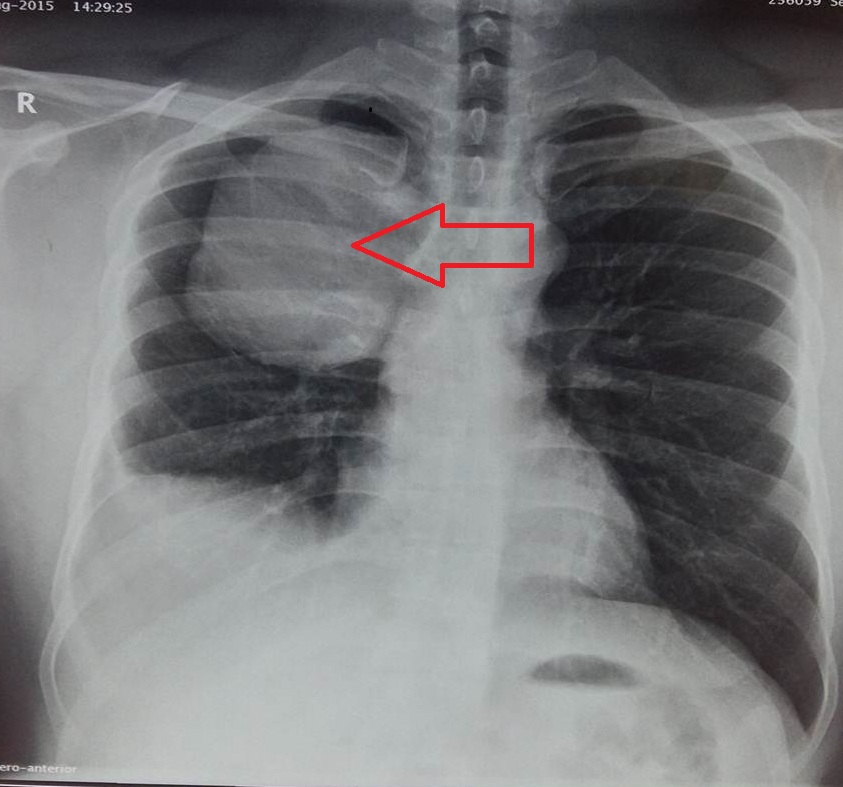

- Figure 3. Right upper lobe mass

- Figure 4. CECT Thorax showing a heterogeneous mass in the posterior aspect of the right upper lobe eroding the rib margin